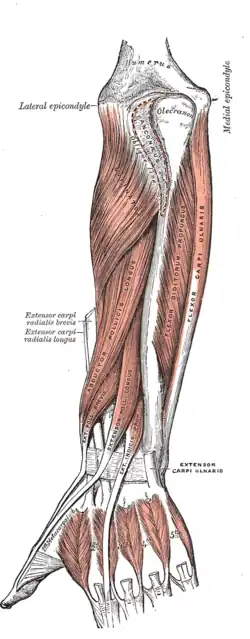

Posterior surface of the forearm. Deep muscles.

Posterior surface of the forearm. Deep muscles. -